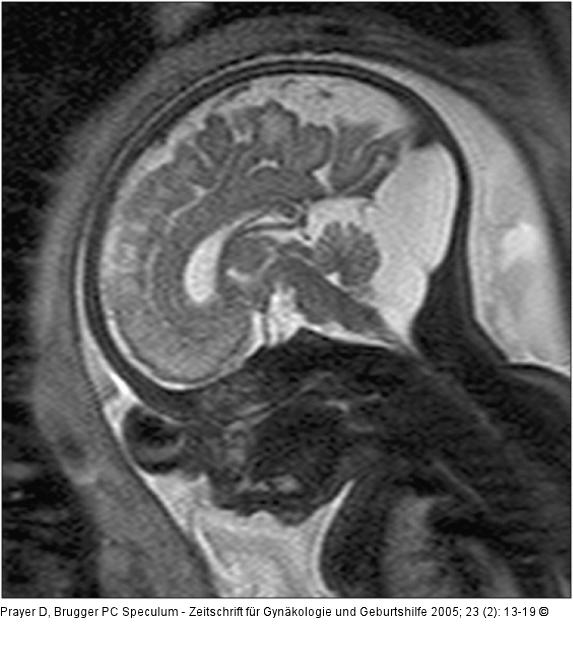

Abbildung 3: Pränatale Magnetresonanztomographie 3: 33 SSW. In dieser sagittalen Schnittführung erkennt man einen hochstehenden Torculus Herophili, eine große hintere Schädelgrube, die von einer zerebellären Falz durchzogen wird, sowie einen sonst unauffälligen Inhalt der hinteren Schädelgrube, wobei insbesonders kein Hinweis auf eine Gewebekompression besteht. Auch supratentoriell regelrechte Verhältnisse. Die Diagnose lautet daher Megazisterna magna. Neurologische Symptome sind hier nicht zu erwarten. |